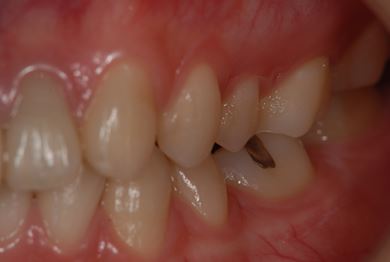

セラミック治療

| 性別/年齢 | 女性 / 20歳 | ||||||||||||||||||||||||||||||||

| 主訴 | 神経が死んで来ている歯が痛むので、治療をして欲しい。歯並びも良くできるのであればして欲しい。 | ||||||||||||||||||||||||||||||||

| 治療方針 | ジルコニアオールセラミック(クラウン1本、ブリッジ3本)、セラミック用土台2本 | ||||||||||||||||||||||||||||||||